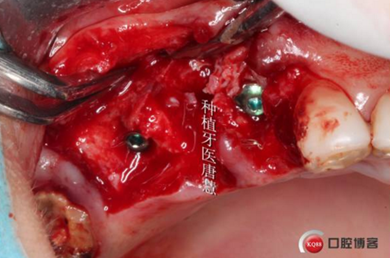

局麻下拔除患牙

切開

翻瓣,肉芽超多

15根尖區(qū)大塊肉芽腫

大量鹽水沖洗后

拔牙窩偏舌側(cè)備洞,13貼面對于植入方向判斷還是有一定迷惑的

逐級備洞

術(shù)中收集的自體骨

植入植體

自體骨填充拔牙窩與植體間空隙

植入骨粉

牙齦乳頭交叉縫合